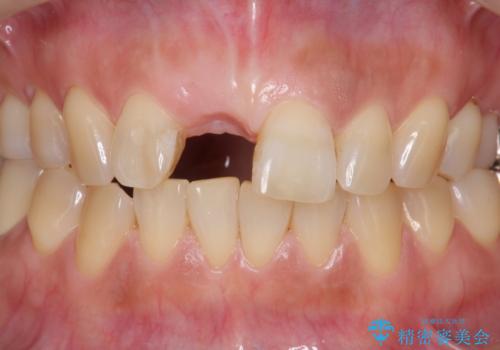

骨造成を伴う前歯のインプラント治療

- 前歯を外傷により失い、審美性の改善を求めて来院されました。

横の歯を削る必要のあるブリッジ治療、着脱の必要な入れ歯に強い抵抗があったためインプラント治療を計画します。

前歯のインプラントを審美的に仕上げるには、インプラント周囲に十分な骨の量と厚みのある歯肉、そして埋入位置の精密な位置付けが重要です。